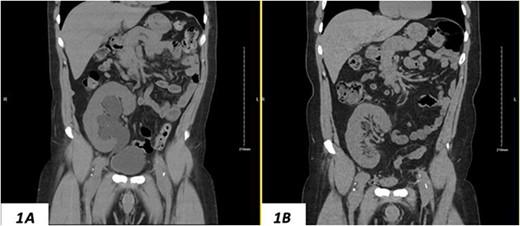

Despite a new onset proteinuria of 50 mg/dl, he continued to have a good functioning graft with a creatinine level of 93 μmol/l corresponding to an estimated glomerular filtration rate (eGFR) of 78 ml/min/1.73 m2. Nonetheless, he had also been noting an inguinal bugle that becomes more prominent as the day progressed, and it regressed at night. Upon further investigations, an ultrasound of the allograft revealed moderate-to-severe hydronephrosis. Further imaging using computed tomography scan (CT) confirmed the presence of upstream moderate hydronephrosis (Figs 1A and2A) along with a reported herniation of the ureter in a right inguinal hernia, resulting in a focal distal ureteric dilatation of 3.5 cm (Fig. 3A).

(A) Hydronephrosis of the allograft ureter on preoperative coronal CT scan; (B) significant improvement of hydronephrosis on the 10-month postoperative image.

The hydronephrosis significantly improved in the 1-year follow-up imaging (Figs 1–3B). The patient continues to enjoy satisfactory graft function with no hernia recurrence. As of July 2023, the patient had further improvement in graft function reflected via a serum creatinine of 76 μmol/l reflecting a eGFR of 99 ml/min/1.73 m2 and 10 mg/dl of proteinuria.